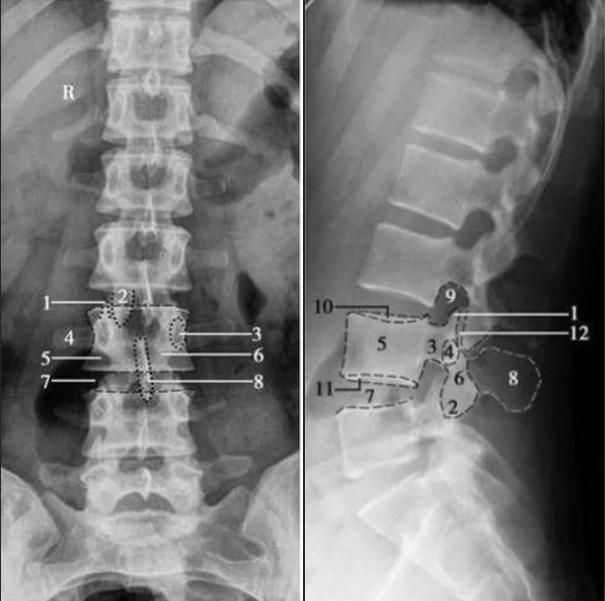

腰椎正側位

1. 上關節(jié)突;2. 下關節(jié)突;3. 椎弓根;4. 橫突;5. 椎體;6. 椎弓板;7. 椎間隙;8. 棘突;9. 椎間孔;10. 椎體上終板;11. 椎體下終板;12. 椎突間關節(jié)